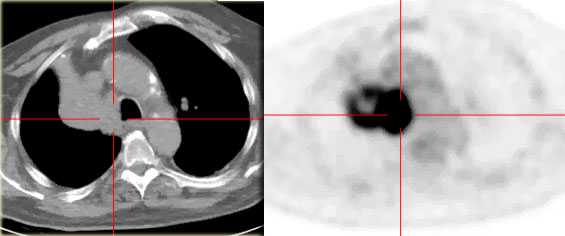

На ПЭТ/КТ визуализируется опухоль легкого с обструкцией правого верхнедолевого бронха, как следствие ателектаз верхний доли правого легкого.

Оцените нижележащие ПЭТ/КТ изображения. Легочная карцинома обтурирующая левый верхнедолевой бронх и правый верхнедолевой бронх. Множественные метастазы в кости. Стрелкой указан метастаз в ребро.